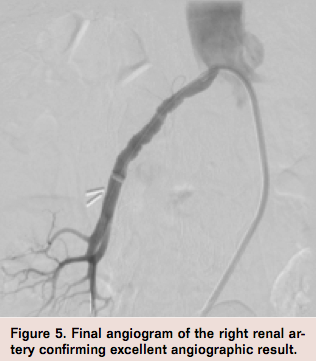

The patient did not experience any discomfort during the cryoplasty. Repeat OCT imaging confirmed a good result with no further irregularities of the vessel wall (Figure 4). Final angiogram confirmed a good angiographic result with brisk flow (Figure 5). The patient was discharged home the following day with a resting systolic blood pressure of 120-130 mmHg. She returned for follow-up at 1 month post procedure with stable blood pressures.